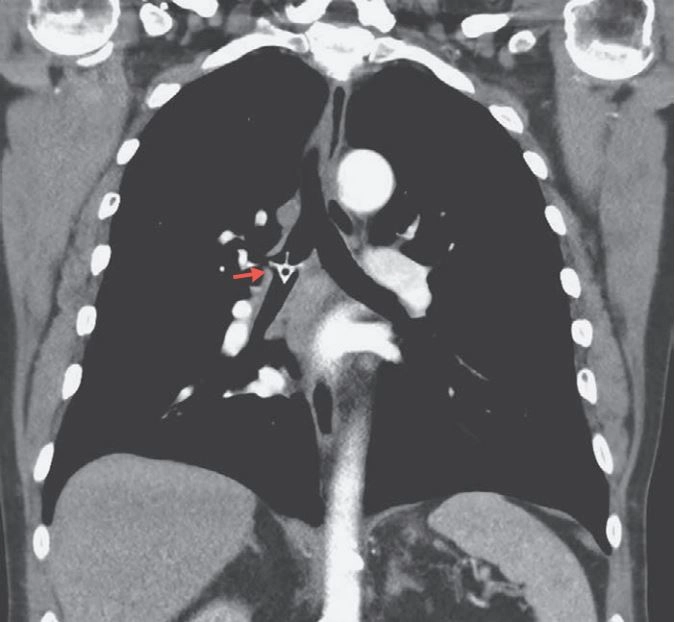

It really did go down the wrong pipe: A striking new image shows a chicken bone lodged in an Australian man's lung. What's more, the bone was stuck there for five days before it was discovered.

This time, doctors performed a CT scan, which showed a chicken vertebra bone in the right "mainstem bronchus," the airway that branches off from the trachea into the lung. An area in the man's right lung wasn't inflating properly, but this symptom was minor, the report said.